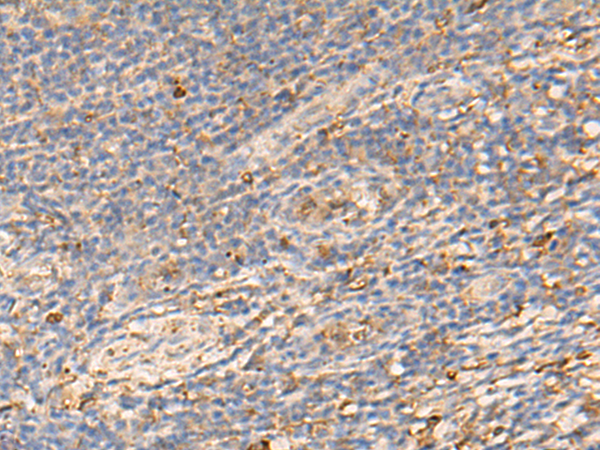

分类: 科研抗体货号: P09886别名: CHED; CHED1; CHED2; PPCD1; ZNF339; EUROIMAGE566589应用: WB,IHC反应种属: Human, Mouse